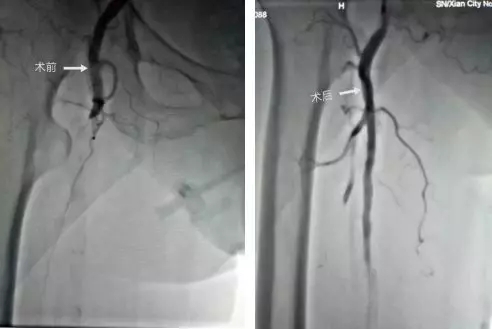

心内五病区成功为一名90岁高龄急性下肢动脉血栓患者行介入取栓溶栓术